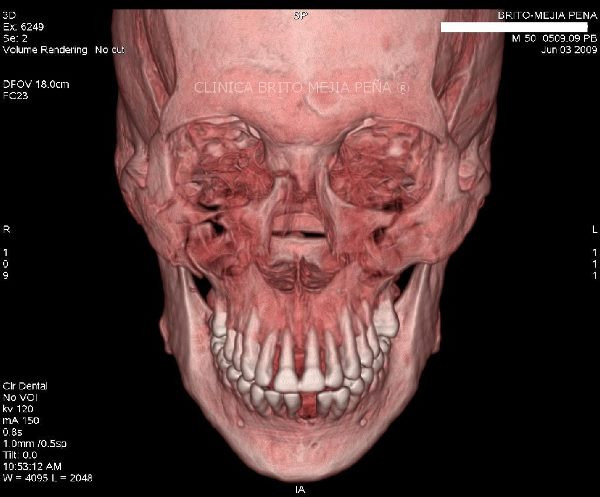

Fractura malar